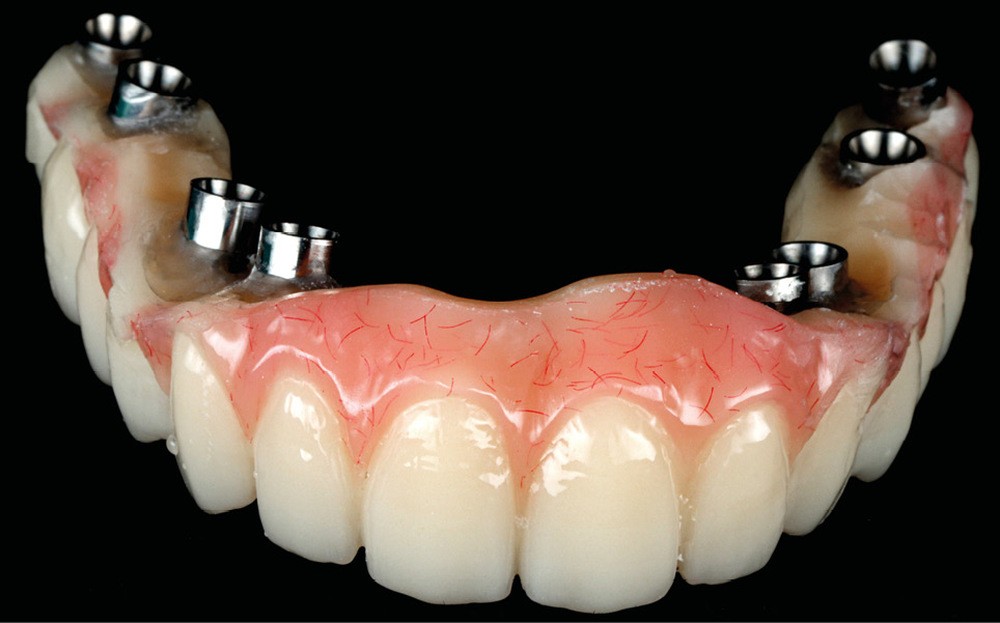

Après une extraction atraumatique des dents résiduelles, nous passons au 3e étage qui est le guide de forage stéréolithographique. La séquence de chirurgie Full guided est passée et les implants ont été torqués entre 40 et 50N.cm2 (fig. 6, 7, 8). Cette stabilité primaire dans les sites d’extraction et des sites greffés a permis la mise en charge immédiate du bridge complet provisoire. Des études cliniques [3, 4, 5] ont montré que la mise en charge immédiate dans les sinus greffés ne pose aucune contre-indication. Le 4e étage est donc celui du bridge provisoire transvissé à l’étage de base et solidarisé en bouche par l’intermédiaire de cylindres provisoires sur piliers MUA, avec une colle duale (GC-LinkForce). L’espace entre les implants et l’alvéole a été comblé par une xénogreffe (Bio-Oss Geistlich). Les profils d’émergence sont travaillés et parfaitement polis. Enfin, le bridge est mis en place, torqué à 20.cm2, équilibré et les consignes postopératoires ont été rappelées à la patiente (fig. 9 et 10).